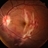

- This fundus photograph shows curvilinear streaks of choroidal rupture radiating from the fovea, associated with subretinal hemorrhage. The rupture lines appear as crescent-shaped, whitish streaks representing a break in Bruch’s membrane, choriocapillaris, and retinal pigment epithelium.